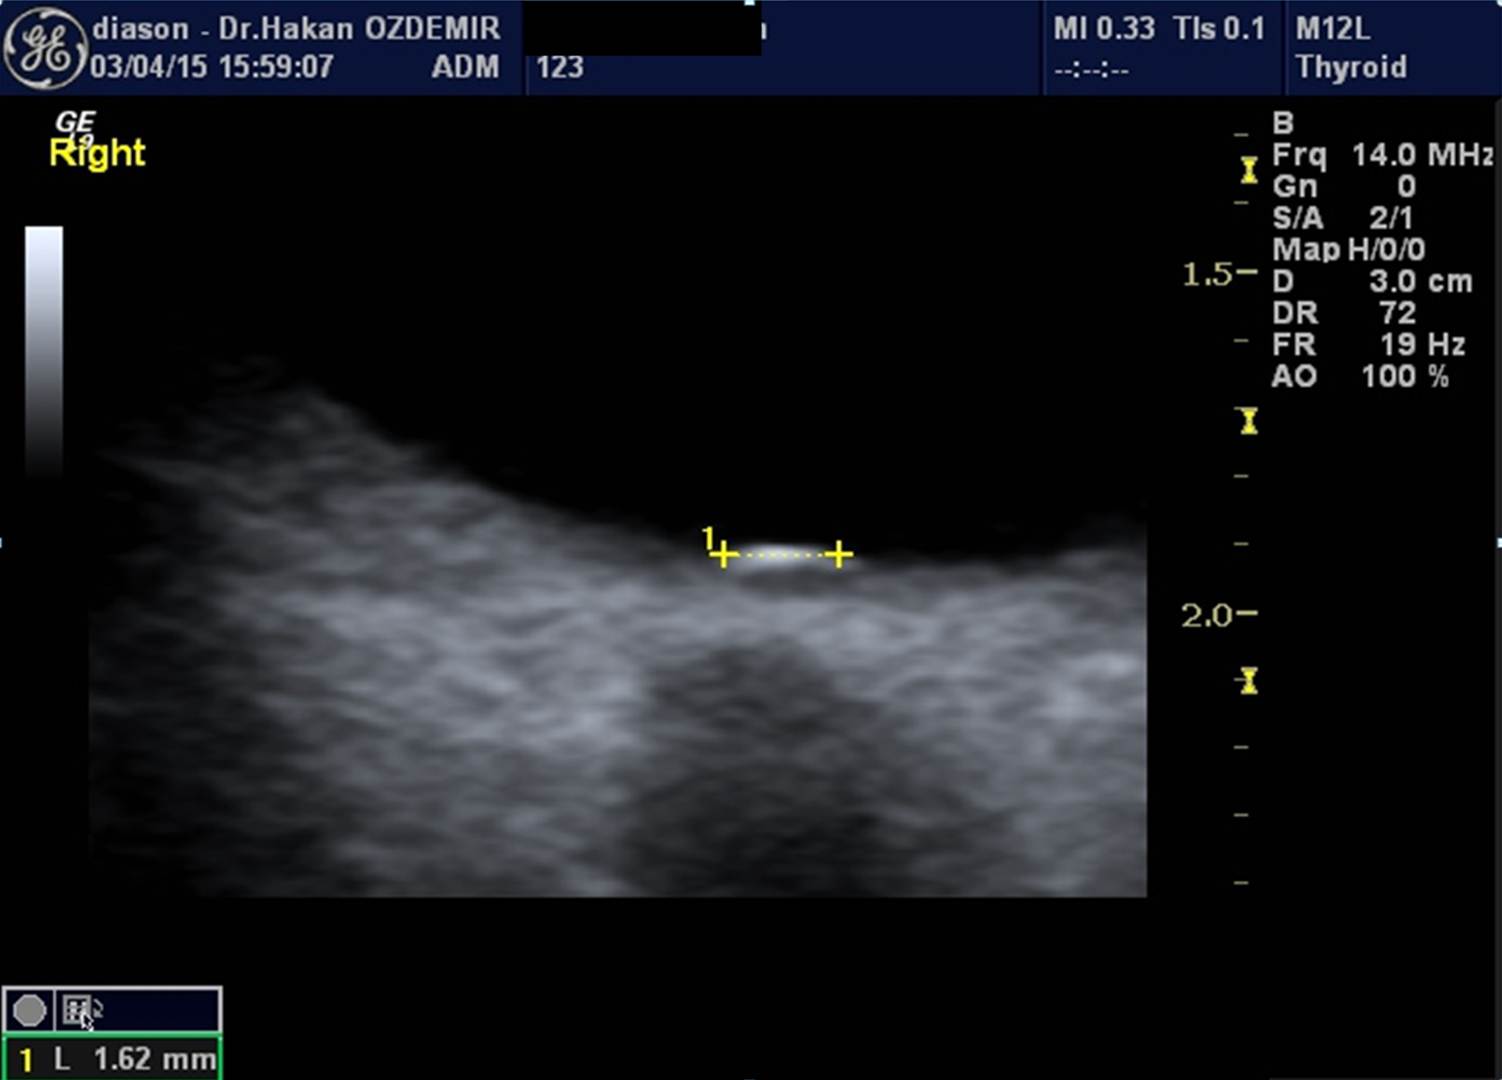

Ultrason, yüksek frekanslı ses dalgaları (ultrases) kullanılarak vücut içindeki organların ve diğer yapıların görüntülenmesi yöntemidir. Ultrasonda kullanılan ses dalgaları insan kulağının işitemeyeceği kadar yüksek frekansa sahiptir. Ultrason görüntülemede iyonizan radyasyon (X-ışınları) kullanılmadığı için bilinen zararlı etkisi bulunmamaktadır.

Ultrason cihazı, içerisinde bilgisayar ve elektronik aletlerin bulunduğu bir konsol, görüntülerin izlendiği bir ekran ve vücudu taramada kullanılan prob (transdüser) dan oluşmaktadır.

İnceleme sırasında prob ile vücut yüzeyi arasındaki temas jel aracılığı ile sağlanmaktadır. İncelenen bölgeye jel sürülmesinin nedenleri yüzeyin kayganlaştırılmasını sağlamak ve probun hava ile temasını önlemektir. Ultrason görüntülemenin temeli, yarasalar ve gemilerin kullandığı "sonar" ile aynıdır. Ses dalgaları vücuttan geçerken oluşan yansımalar, objenin uzaklığı, büyüklüğü, şekli ve yoğunluğunu tanımlamada kullanılır.

Ultrason probları, hem ses üreteci (hoparlör) hem de ses alıcısı (mikrofon) olarak çalışır. Prob cilde bastırıldığında vücut içine yüksek frekanslı, duyulamayan ses dalgaları yollar. Ses dalgaları vücuttaki doku ve sıvılardan yansıdıkça, prob yansıyan dalgaların özelliğini ve şiddetini kaydeder. Doppler ultrason da ise, prob ses dalgalarının yönü ve şiddetindeki küçük değişiklikleri kaydeder.

Bu yansımalar prob içinde bulunan özel kristaller aracılığıyla elektrik sinyallerine dönüştürülür. Daha sonra cihazın içinde yeralan bilgisayar aracılığı ile bu sinyallerden ekranda izlenen gerçek zamanlı görüntüler oluşturulur.